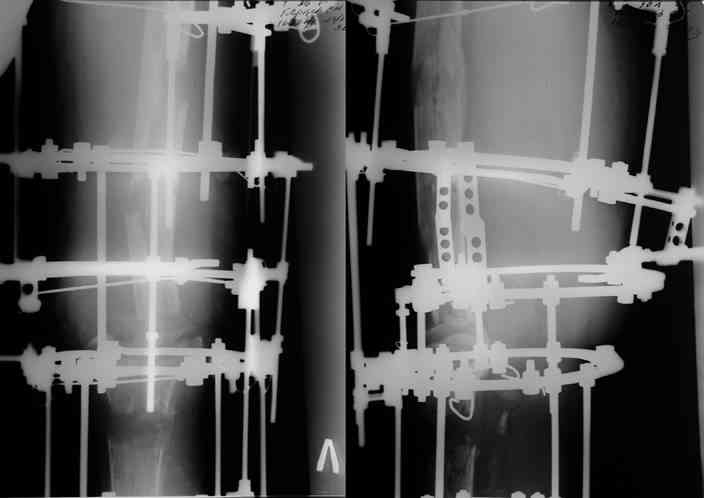

Через 3 года после травмы констатировало отсутствие консолидации бедренной кости, сохранение признаков хронического остеомиелита (свищ в нижней трети левого бедра). Произведен демонтаж аппарата, реостеосинтез бедренной кости спице-стержневым аппаратом, некрсеквестрэктомия. В аппарате удалось лишь частично произвестиустранение углообразной деформации бедренной кости [image 05] .

Через 4,5 лет после травмы выявлены рентгенологические признаки консолидации перелома, признаки хронического остеомиелита купировались. Аппарат был демонтирован. Пациент продолжил ходьбу с дозированной нагрузкой на конечность при помощи костылей. Через 2 месяца начал ходить при помощи трости. Однако, еще через 2 месяца отметил появление свищей на бедре с гнойным отделяемым и укорочение длины конечности. При осмотре в январе 2007 г.: пациент ходит при помощи костылей без опоры на левую нижнюю конечность, на бедре имеются множественные рубцы, на наружной поверхности сегмента в верхней и нижней третях имеются два свищевых хода со скудным серозно-гнойным отделяемым; отечности тканей конечности нет, пальпация безболезненная, отмечается укорочение длины конечности на 5 см, патологическая подвижность не определяется, имеется стойкая разгибательная контрактура коленного сустава (разгибание - 180 гр, сгибание - 170 гр), признаков нарушения кровоснабжения и иннервации тканей конечности нет. Температура тела нормальная. В общих анализах крови и мочи отклонений от нормы нет. [image 06,07, 08 (стрелками отмечены свищевые раны, 09, 10]Дорогие коллеги, я уверен, что у многих из вас после знакомства с данным клиническим наблюдением появится множество вопросов, касающихся уже проведенного лечения (особенно, сроков и способов). Сразу оговорюсь - я не смогу правильно ответить на многие вопросы (особенно касающиеся предшествующего периода лечения). Прошу вас, конечно по возможности, сосредоточить внимание не на разборе допущенных ошибок (проведенного лечения), а помочь добрым советом относительно тактики наших дальнейших действий. Наверное, кто-то располагает бесценным опытом лечения подобной патологии.